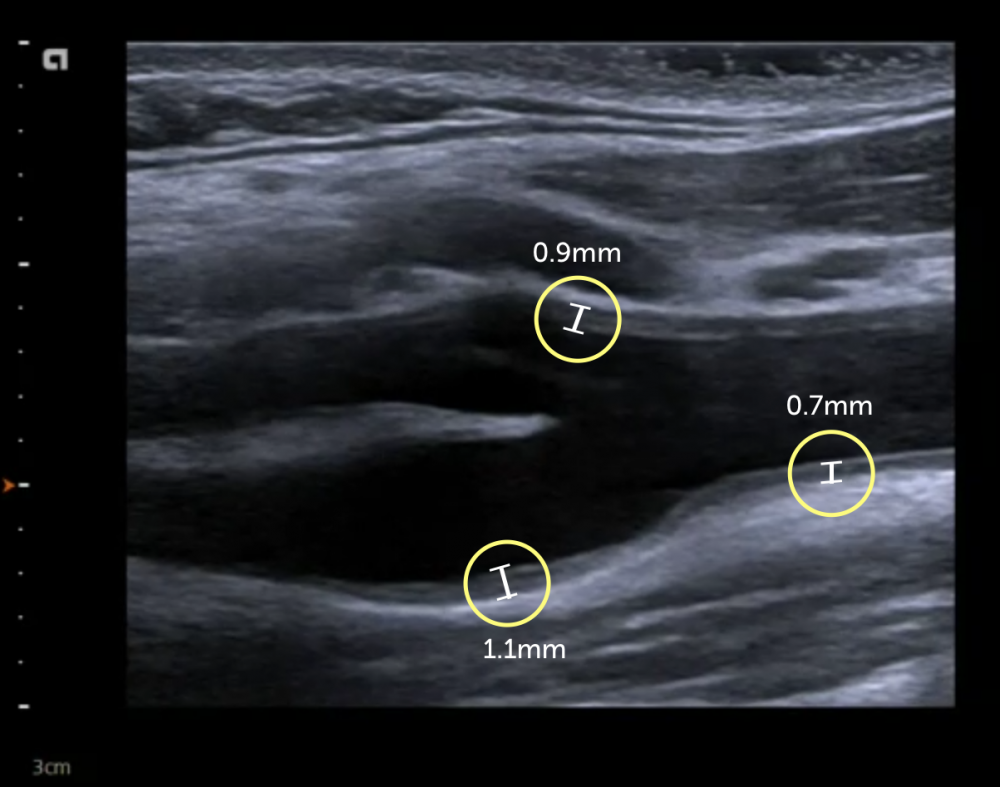

Intima Media Thickness (IMT) Ultrasound is a diagnostic procedure that measures the thickness of the inner walls of arteries. By assessing the carotid arteries in the neck, it provides critical information about plaque buildup and arterial health. This test is an important tool for evaluating cardiovascular risk, identifying early signs of heart disease, and determining the likelihood of stroke. It is an FDA-approved, non-invasive, and painless procedure that requires no radiation, making it a safe and effective screening option.

IMT Ultrasound helps in identifying early signs of atherosclerosis, a condition where plaque builds up in the arteries. By detecting plaque buildup, this screening allows physicians to assess the risk of heart disease or stroke, even before symptoms appear. Early identification means timely intervention, allowing doctors to recommend treatments or lifestyle changes to reduce the risk of heart attacks or strokes, potentially saving lives.

You will typically receive your IMT Ultrasound results within a few days after the procedure. The findings will include a detailed report of your artery health, including the thickness of your arteries and any signs of plaque buildup. The results will help your doctor make informed decisions about your cardiovascular health and whether any follow-up treatments or lifestyle adjustments are necessary.